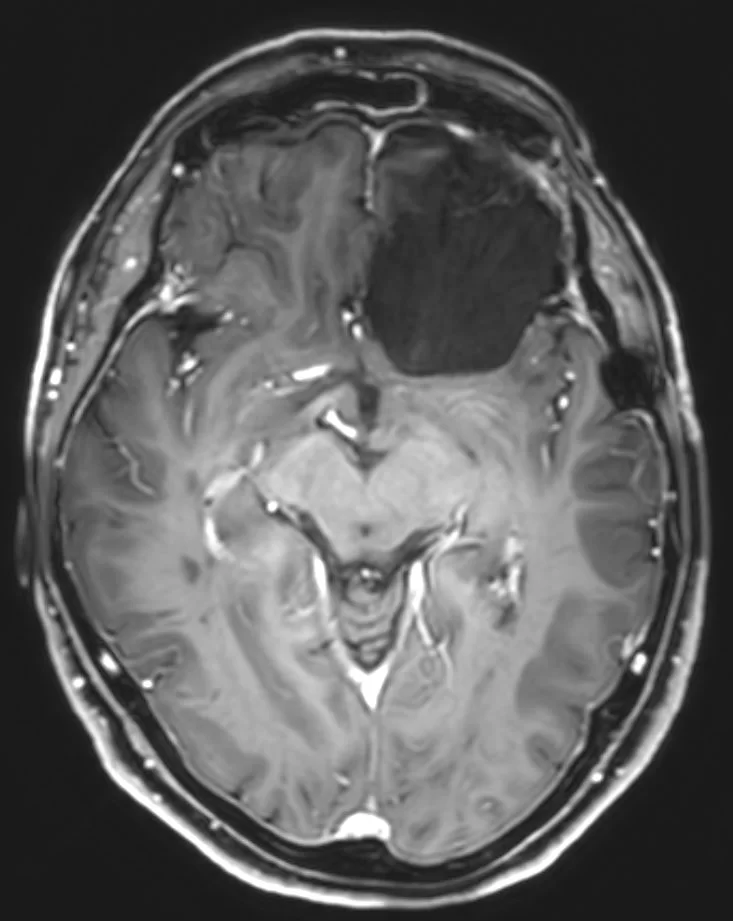

Η μετεγχειρητική μαγνητική τομογραφία εγκεφάλου δείχνει ολική εξαίρεση. Η ιστολογική εξέταση ανέδειξε μηνιγγίωμα (WHO I).

Πρόκειται για ένα ιδιαίτερα μεγάλο μηνιγγίωμα, στην επικρατούσα πλευρά (αριστερά), το οποίο πίεζε δομές όπως τα οπτικά νεύρα και είχε «ενσωματώσει» σημαντικά αγγεία του εγκεφάλου (αριστερή καρωτίδα και κλάδους της). Όγκοι σαν και αυτόν χρειάζονται υπομονή και καλή μικροχειρουργική τεχνική προκειμένω να παρασκευαστούν και να προφυλαχθούν όλα τα κρίσιμα αγγεία. Η υποχώρηση των συμπτωμάτων ήταν άμεση.